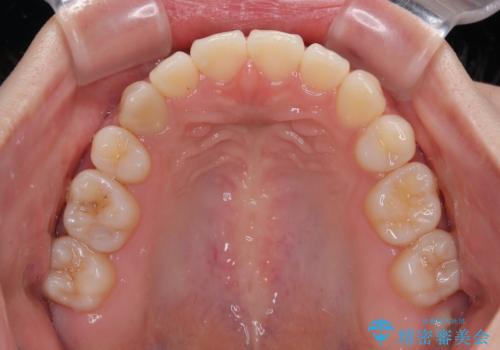

舌のトレーニングをしっかりと行ってくださり、予定通りの期間で理想的な仕上がりを達成することができました。

- 口元の突出感と上下前歯のズレを気にして来院された患者様です。

突出感改善のため、上下左右の第一小臼歯4本を抜歯し、ワイヤー装置にて矯正治療を行うこととしました。